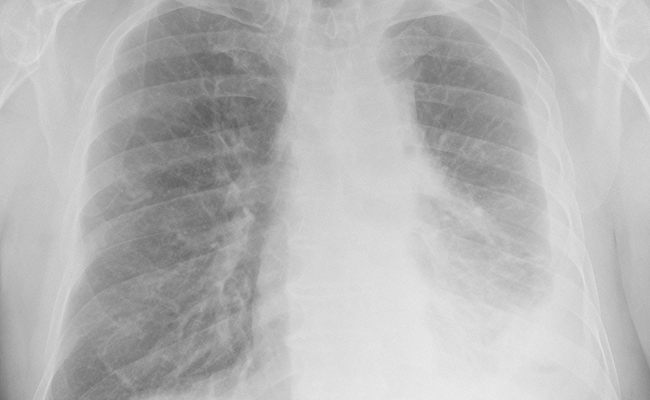

Mesothelioma can develop for years without showing any signs. Sometimes it is discovered earlier when a chest X-ray is taken for unrelated reasons. If it progresses far enough for symptoms before it is discovered, those symptoms can include: